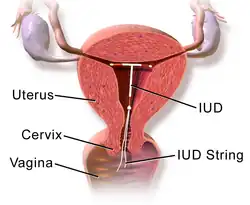

Estrogens and progestogens are the main hormone drugs used in HRT. Progesterone is the main female sex hormone that occurs naturally and is also manufactured into a drug that is used in menopausal hormone therapy.[1] Although both classes of hormones can have symptomatic benefit, progestogen is specifically added to estrogen regimens, unless the uterus has been removed, to avoid the increased risk of endometrial cancer. Unopposed estrogen therapy promotes endometrial hyperplasia and increases the risk of cancer, while progestogen reduces this risk.[3][4] Androgens like testosterone are sometimes used as well.[5] HRT is available through a variety of different routes.[1][2]

In women with intact uteruses, estrogens are almost always given in combination with progestogens, as long-term unopposed estrogen therapy is associated with a markedly increased risk of endometrial hyperplasia and endometrial cancer.[1][2] Conversely, in women who have undergone a hysterectomy or do not have a uterus, a progestogen is not required, and estrogen can be used alone. There are many combined formulations which include both estrogen and progestogen.

- Less commonly sublingual, buccal, intranasal, and rectal administration, as well as intrauterine devices